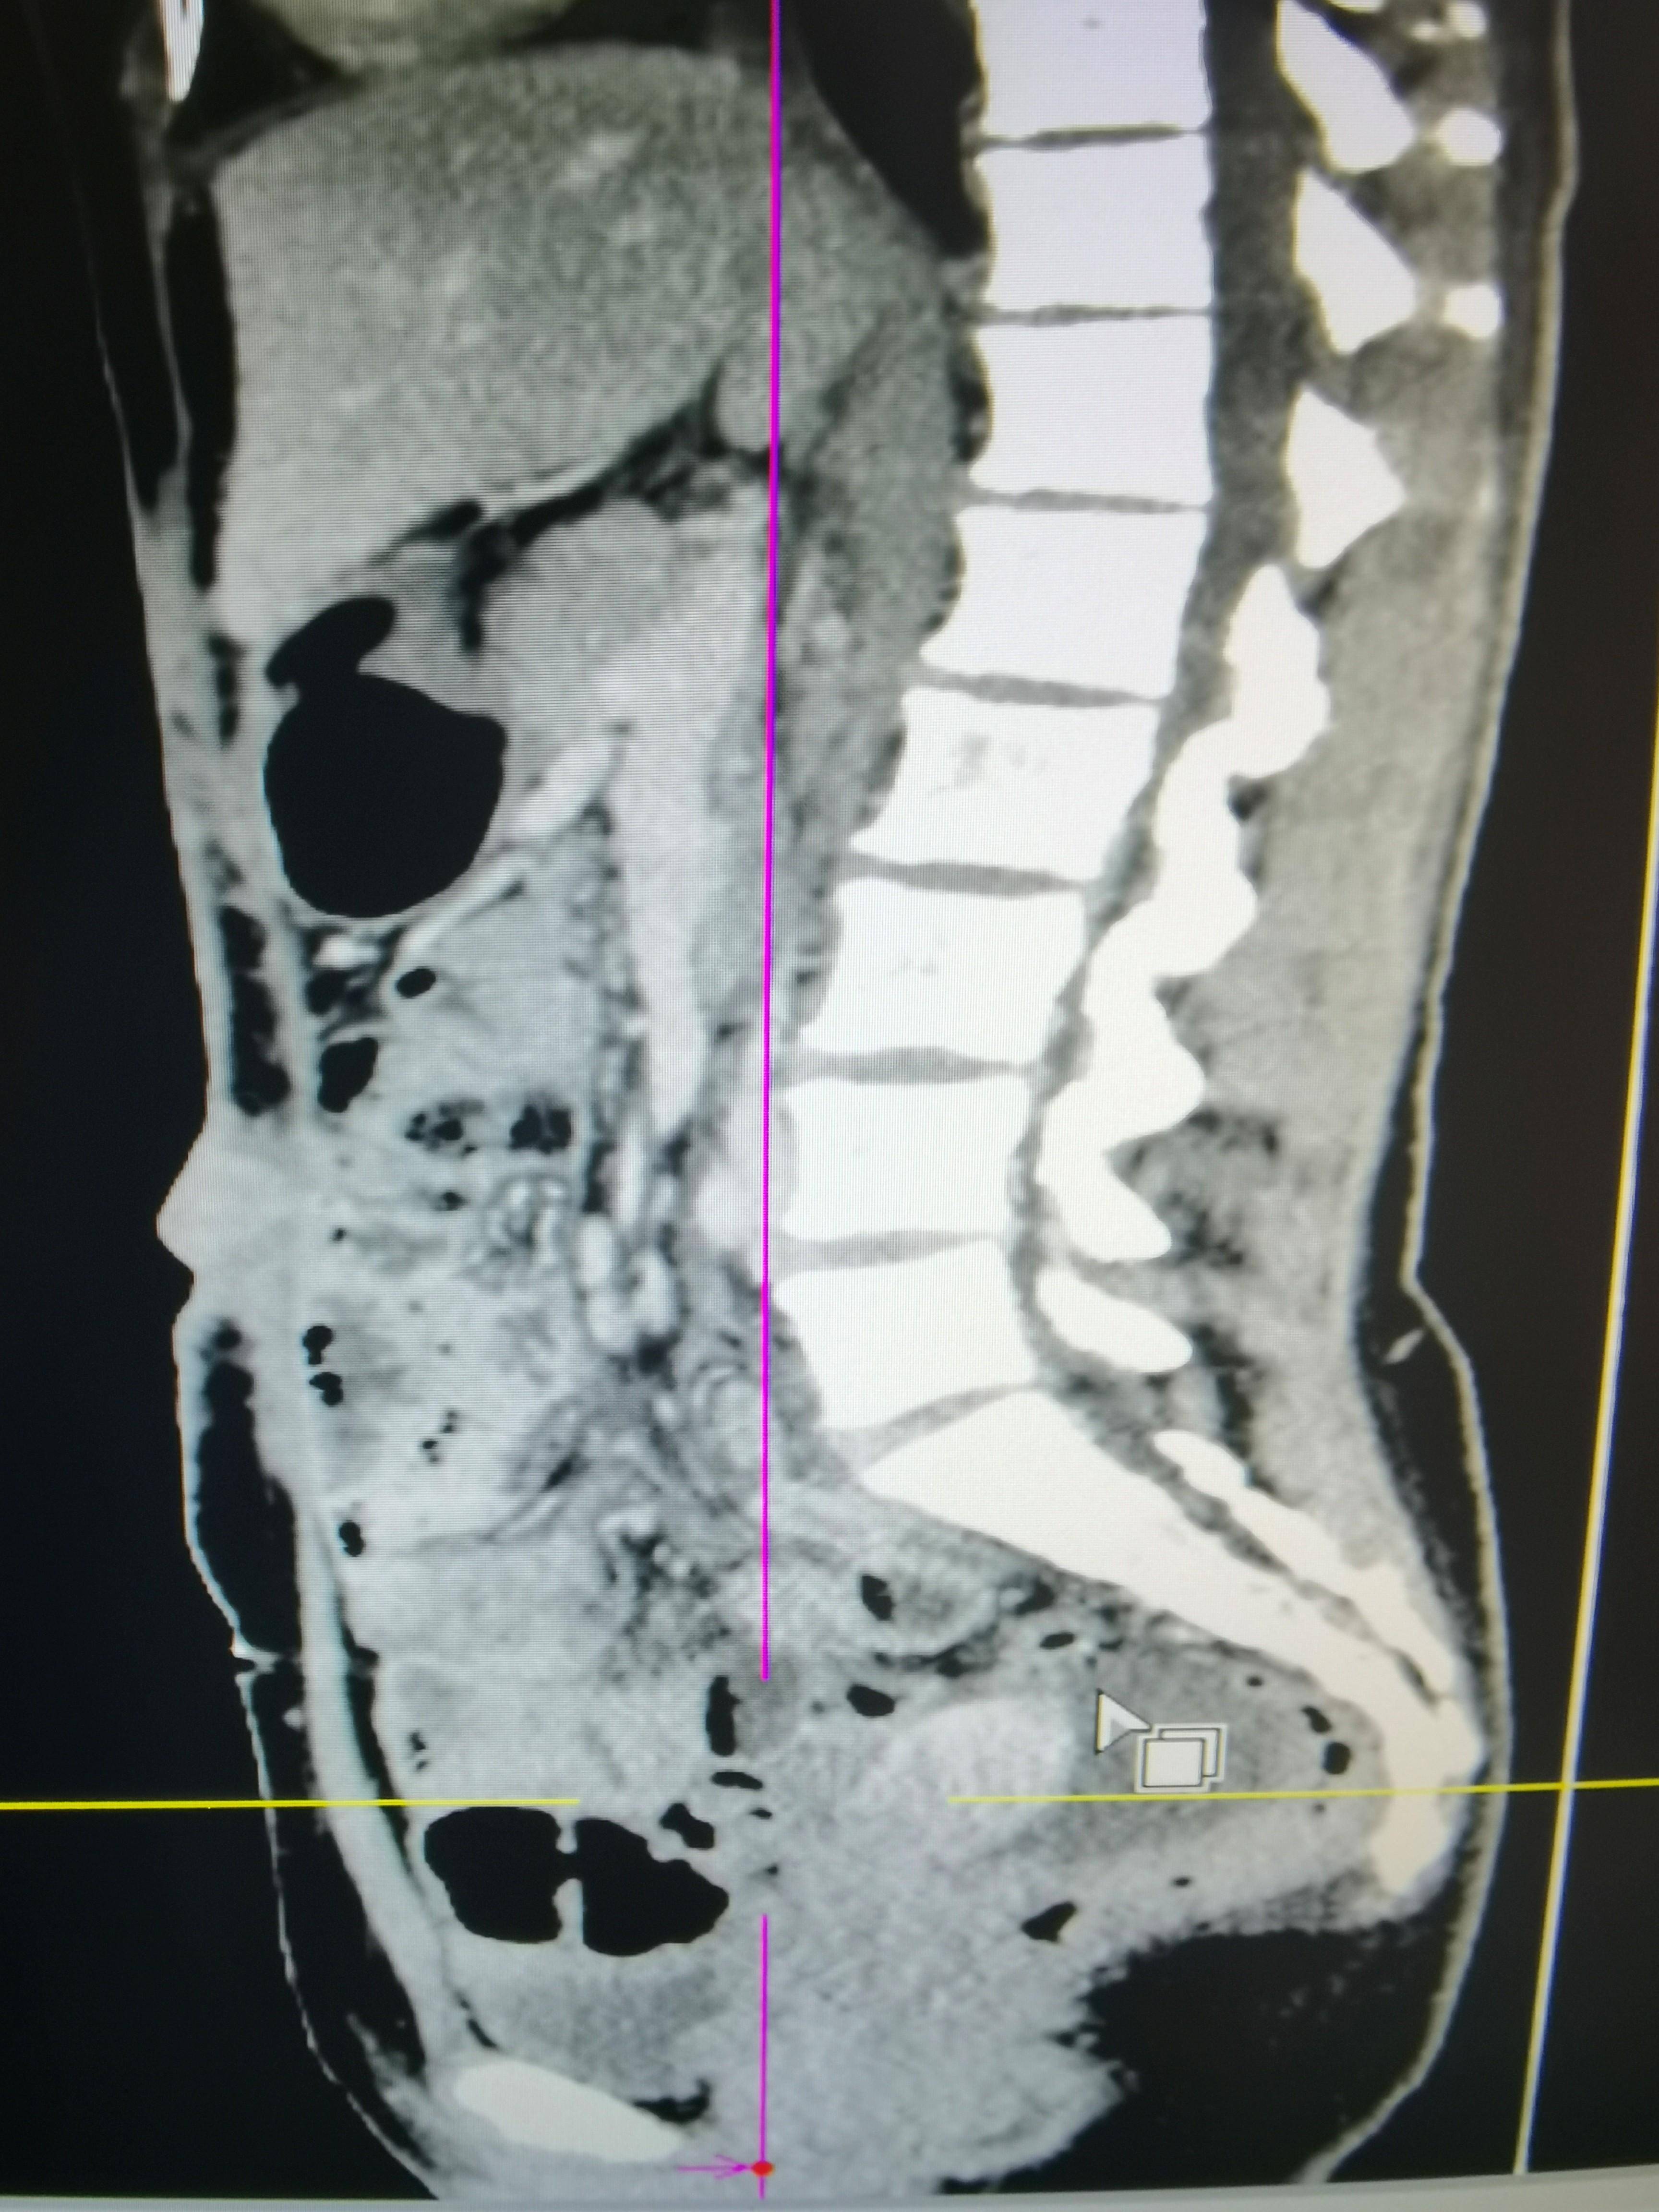

◈ 2022年7月15日,行腹部CT检查提示:盆腔见较大不规则形混杂密度影,与双侧附件及邻近肠管、右侧髂血管分界不清,最大层面约12.4cm×8.8cm,病变上下径约14.9cm,三期CT值约为28Hu、27Hu、31Hu,其内密度不均,可见片状高密度影及钙化密度影,病变周围似见稍高密度包膜影。左上腹部小肠旁另见一相同性质肿块,约4.9cm×3.2cm,边缘强化,与局部肠管分界不清。腹腔内见较多液体密度影。网膜略增厚。

◈ 检查诊断:1、盆腔占位病变,对比2022-04-30片体积稍减小、强化减低。2、腹腔积液,对比前片积液量明显增加;网膜略增厚,请结合临床。3、左上腹部小肠占位性病变,请注意复查。

◈ 考虑肿瘤进展(PD),并且左上腹部小肠占位,考虑转移,腹水量增大。

2022年7月15日 腹部CT